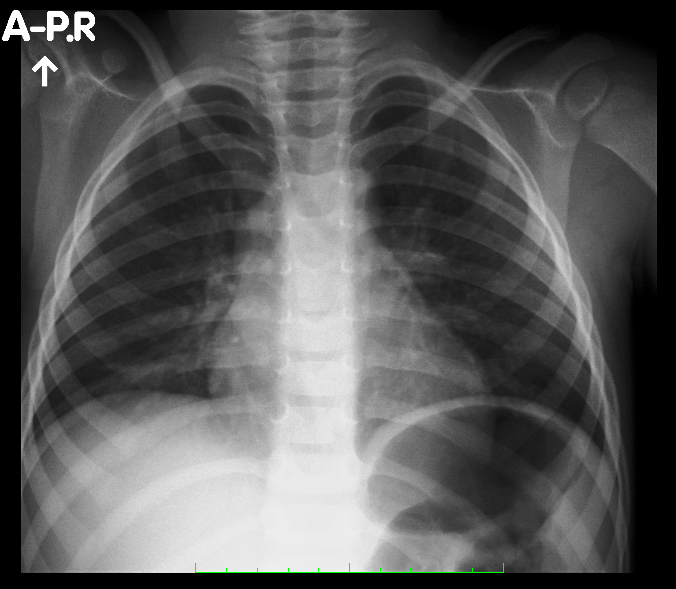

no to #Leon ma pierwsze zapalenie płuc

Pobierz obrazek (319.1kiB)